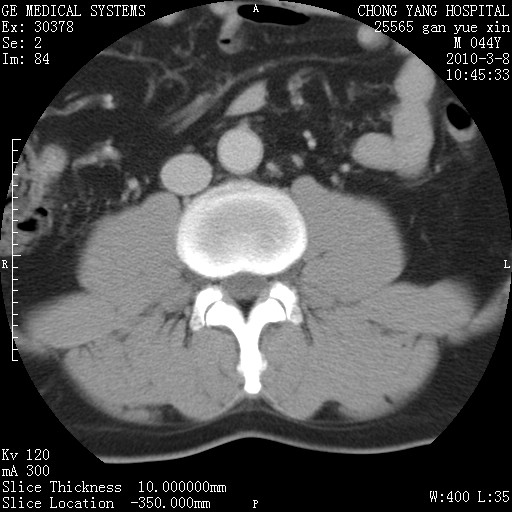

标题: CT24940:主动脉增强,典型病例。 [打印本页]

标题: CT24940:主动脉增强,典型病例。

夹层动脉瘤。

动脉夹层

夹层动脉瘤,典型

主动脉夹层。

动脉夹层的分型:

⒈debakey分型:根据主动脉夹层累及部位,分为三型:ⅰ型:原发破口位于升主动脉或主动脉弓部,夹层累及升主动脉、主动脉弓部、胸主动脉、腹主动脉大部或全部,少数可累及髂动脉。ⅱ型:原发破口位于升主动脉,夹层累及升主动脉,少数可累及部分主动脉弓。ⅲ型:原发破口位于左锁骨下动脉开口远端,根据夹层累及范围又分为ⅲa,ⅲb。ⅲa型:夹层累及胸主动脉。ⅲb型:夹层累及升主动脉、腹主动脉大部或全部。少数可累及髂动脉。

⒉stanford分型:a型:夹层累及升主动脉,无论远端范围如何。b型:夹层累及左锁骨下动脉开口以远的降主动脉。

夹层动脉瘤,少量胸水

夹层动脉瘤;左侧少量胸腔积液。

典型主动脉夹层。